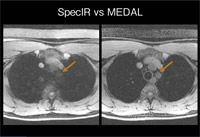

息止めが必要な上腹部や胸部などの領域には、MEDAL(W.I.P.)という2-point Dixon法が有用である。図5のように、SpecIR(LAVA)とMEDALを比較すると、MEDALでは脂肪が抑制され、上縦隔の血管構造が明瞭に描出されている。

図5

図5 MEDAL(W.I.P.)